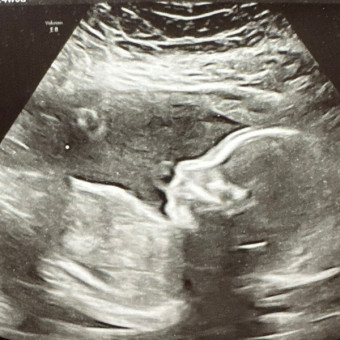

We are so excited to welcome our baby girl, Millie